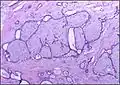

| Histopathologic image of breast fibroadenoma. Core needle biopsy. H&E stain. | |

Microscopic

Fibroadenoma of the breast is a benign tumor composed of a biplastic proliferation of both stromal and epithelial components.[12][13] This biplasia can be arranged in two growth patterns: pericanalicular (stromal proliferation around epithelial structures) and intracanalicular (stromal proliferation compressing the epithelial structures into slit-like spaces).

These tumors characteristically display hypovascular stroma compared to malignant neoplasms.[2][14][9] Furthermore, the epithelial proliferation appears in a single terminal ductal unit and describes duct-like spaces surrounded by a fibroblastic stroma. The basement membrane is intact.[15]

.jpg) Fibroadenoma histology (H&E). The image demonstrates intracanalicular morphology (bottom left) and pericanalicular morphology (top right)

Fibroadenoma histology (H&E). The image demonstrates intracanalicular morphology (bottom left) and pericanalicular morphology (top right) -

.jpg) Histopathologic image of breast fibroadenoma. Core needle biopsy. Hematoxylin & eosin stain.

Histopathologic image of breast fibroadenoma. Core needle biopsy. Hematoxylin & eosin stain. -

Histopathologic image of breast fibroadenoma showing proliferation of intralobular stroma compressing and distorting the epithelium. H&E stain.

Histopathologic image of breast fibroadenoma showing proliferation of intralobular stroma compressing and distorting the epithelium. H&E stain. -